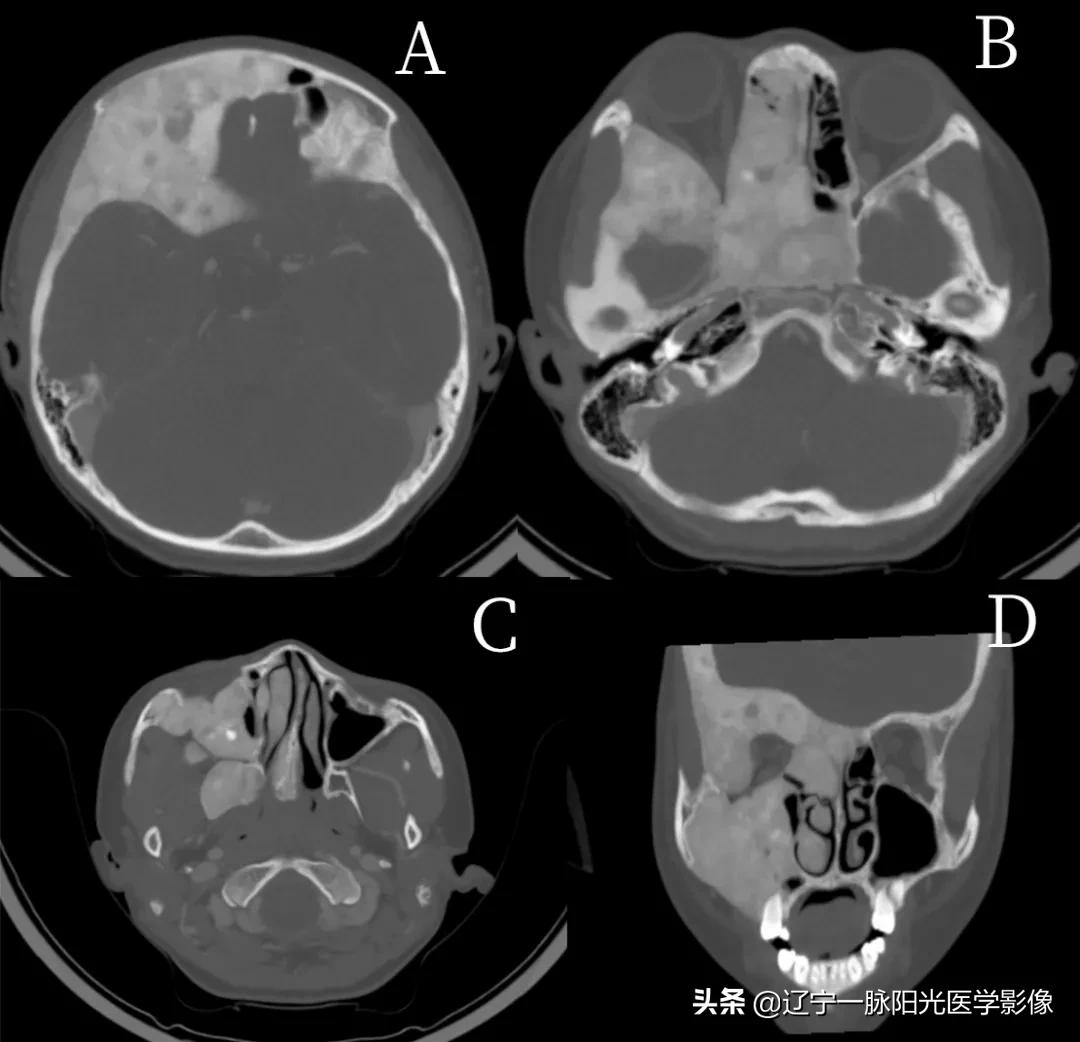

影像所见:

图 A-D 轴位及冠状位示右侧上颌窦、右侧筛窦、右侧颧骨、额骨右侧及颅底部分骨质密度一致性增高,呈磨玻璃样改变,其内见棉花团样密度增高影及小囊状透光区;右眼眶变形,右侧眼球前凸

最终诊断:右侧颌面骨骨纤维结构不良